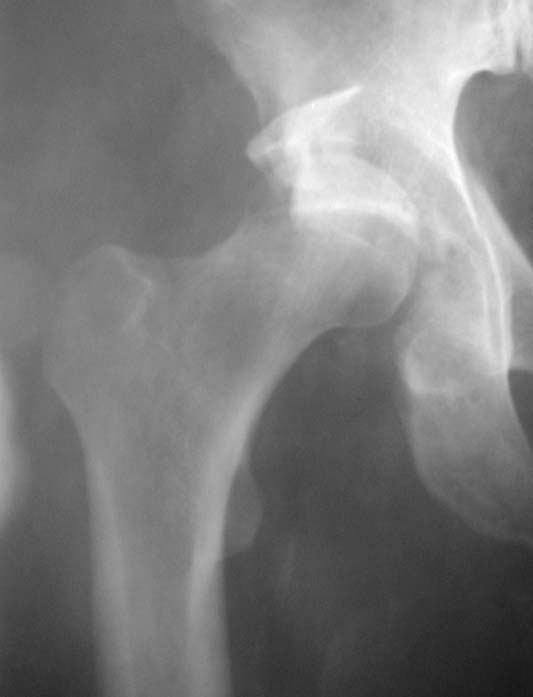

Уважаемые коллеги!Мужчина, 40 лет. Травма несколько месяцев назад. Получил закрытый вывих правого тазобедренного сустава и перелом вертлужной впадины (сним.1).Лечился скелетным вытяжением. Сейчас (сним.2) жалобы на боли, ограничение движений. Вопрос: тактика лечения (эндопротезирование и/или восстановительная операция, иное)?С уважением,А.В.Владзимирский

Нексколько - это все-таки сколько? Если 2-3 - одни планы, 6-8 - другие.

Вывих, похоже, вообще не был устранен. Или из-за дефекта заднего края сразу рецидивировал.

Для уточнения величины дефекта задней стенки и состояния головки необходима КТ. Если МРТ доступна, то и ее.

Если головка живая, прошло менее 2 мес., то мы бы наложили аппарат, стянули бедро дистально за неделю, потом открыто выполнили бы вправление с реконструкцией заднего края, скорее всего с аутопластикой, и фиксировали мостовидной пластиной (чтобы не мешало в дальнейшем эндопротезу).

Если срок больше, головка плохая, и дефект незначительный, то сразу эндопротезирование. Если значительный дефект и будут сложности, то

предусмотреть усложнение операции эндопротезирования из-за той или иной реконструкции впадины (аутопластика, остеосинтез края, укрепляющее кольцо).